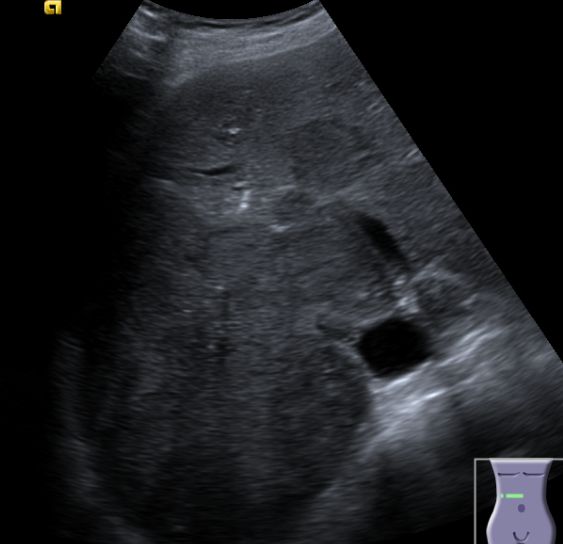

| intrahepatische Filiae | 68-jähriger Mann mit bekannter Leberzirrhose nach Alkoholabusus.

Im CT mehrere hypervaskuläre Herde gesehen.

Im MR beste Darstellung auf den Spätaufnahmen nach leberspezifischem Kontrastmittel in der hepatobiliären Ausscheidung.

Unterhalb der Zwerchfellkuppel links subkapsulär ventral gelegener Herd im 2. Segment 34 mm.

In der koronaren Schichtung im 8.Lebersegment ein 8,5 mm kleiner signalabgesenkter Leberherd.![]() |